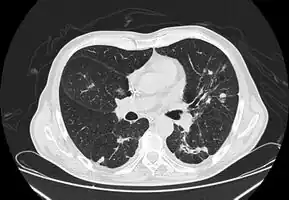

CT chest: Paracoccidioidomycosis

In the juvenile form, lung abnormalities are shown in high-resolution CT scans of the lungs, whereas in the chronic form plain X-rays may show interstitial and alveolar infiltrates in the central and lower lung fields.[14]